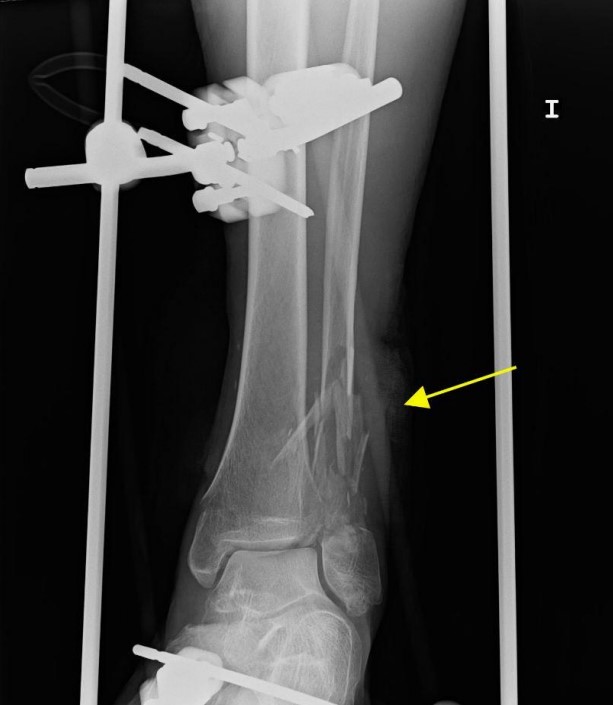

患者左下肢X線片顯示腓骨和脛骨骨折。胸片顯示上肺葉雙側(cè)肺泡混濁,這些不明確的斑片狀氣腔模糊是非特異性的,可見于肺水腫、誤吸或感染。繼續(xù)為患者行胸部CT檢查,CT顯示肺動脈干、左或右肺動脈主干或肺葉動脈無充盈缺損,雙側(cè)胸腔積液。肺窗顯示雙側(cè)上、左中肺野斑片狀磨玻璃影伴小葉間隔增厚。

圖1 左下肢X片。外固定器處理腓骨和脛骨骨折移位(黃色箭頭)